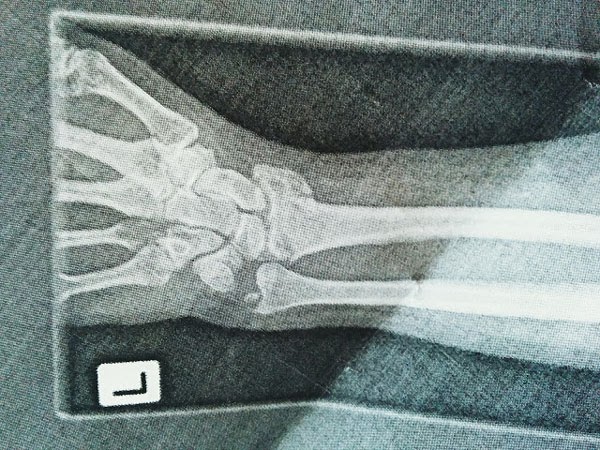

Non-eventful drive to the North Shore Hospital to be assessed, x-rayed and diagnosed... impacted intra-articular fracture of left distal radius with ulnar styloid fracture. In layman's terms my ulnar and radius had tried to force themselves under my wrist.... fuck!